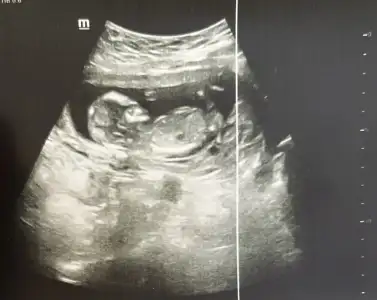

Kızlar bugün 13+0 oldum. İkili test verdim. Doktor çok profesyoneldi. Devlet hastanesinde erken söylemiyorlar diye sormaya da utandım. Sizce neye benziyo? Ctesi ilk bebeğimin doğumunu yaptıran doktora randevum var orda öğrenirim gibi geliyor ama yorumlarınızı merak ettim.